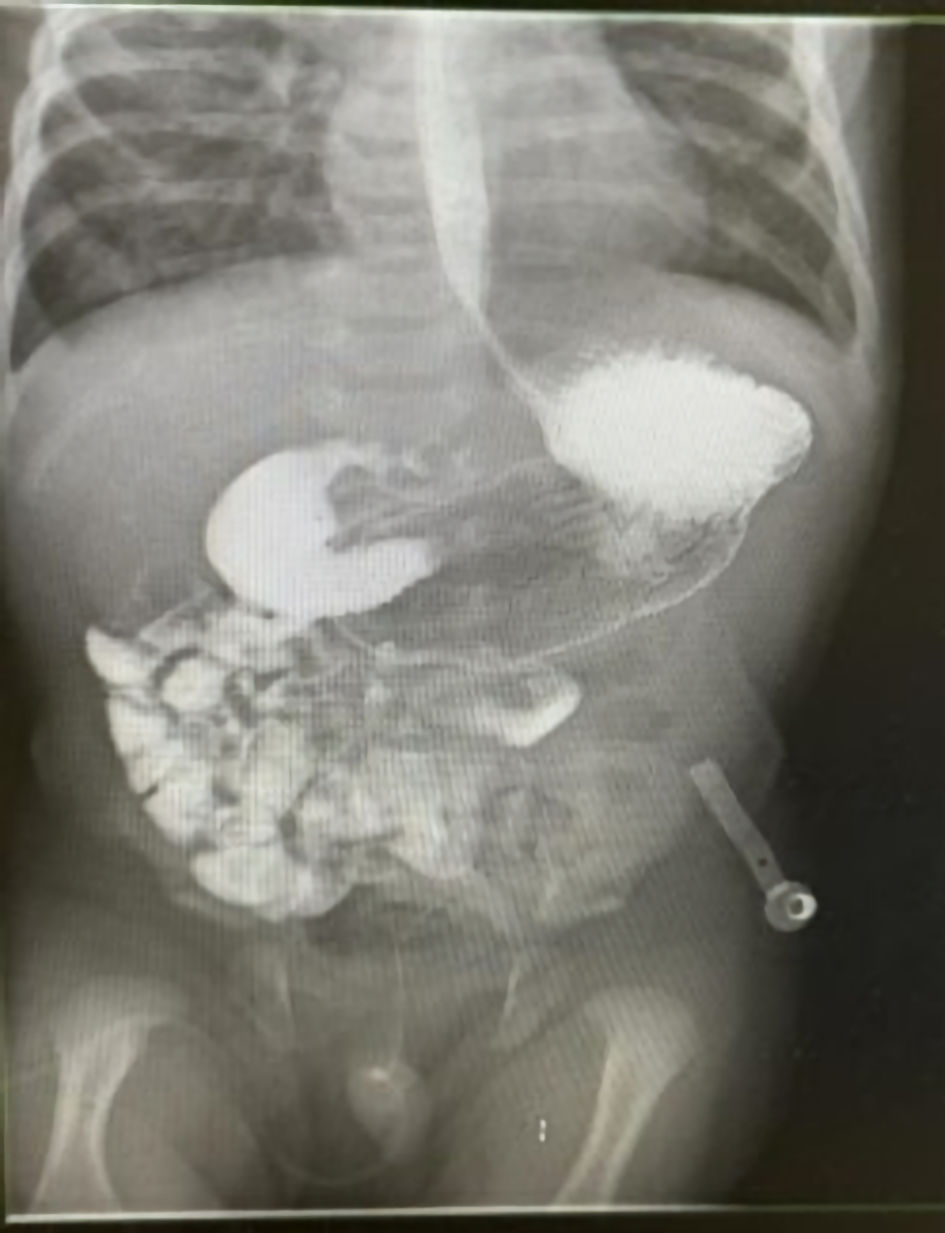

An abdominal X-ray demonstrated a single large bubble (Fig. 2), prompting an urgent surgical consultation. Laboratory results confirmed severe dehydration, with elevated creatinine and urea levels, coagulopathy characterized by a significantly elevated international normalized ratio (INR), and elevated lactate levels with a metabolic alkalosis on venous blood gas, all suggestive of hypoperfusion and systemic compromise.

Figure 2. An abdominal X-ray demonstrated a single large bubble.

After the patient’s condition stabilized, the surgery team conducted an UGI study (Fig. 3), which was suboptimal due to the unavailability of early oblique images to assess the duodenum and duodenojejunal junction orientation. Nevertheless, the study revealed dilatation of the stomach and duodenal “C” loop, with possible narrowing at the duodenum or pylorus and jejunal loops positioned on the right, suggestive of malrotation.

Figure 3. An upper gastrointestinal (UGI) study revealed dilatation of the stomach and duodenal “C” loop, with possible narrowing at the duodenum or pylorus and jejunal loops positioned on the right, suggestive of malrotation.

The diagnostic approach typically begins with abdominal X-ray, followed by UGI contrast, which is the gold standard [8]. However, UGI can be inconclusive in up to 15% of cases, as occurred here, where the duodenojejunal junction was difficult to assess [11]. Ultrasound has emerged as a useful adjunct, particularly when UGI results are unclear, though its accuracy remains operator-dependent [11, 12].